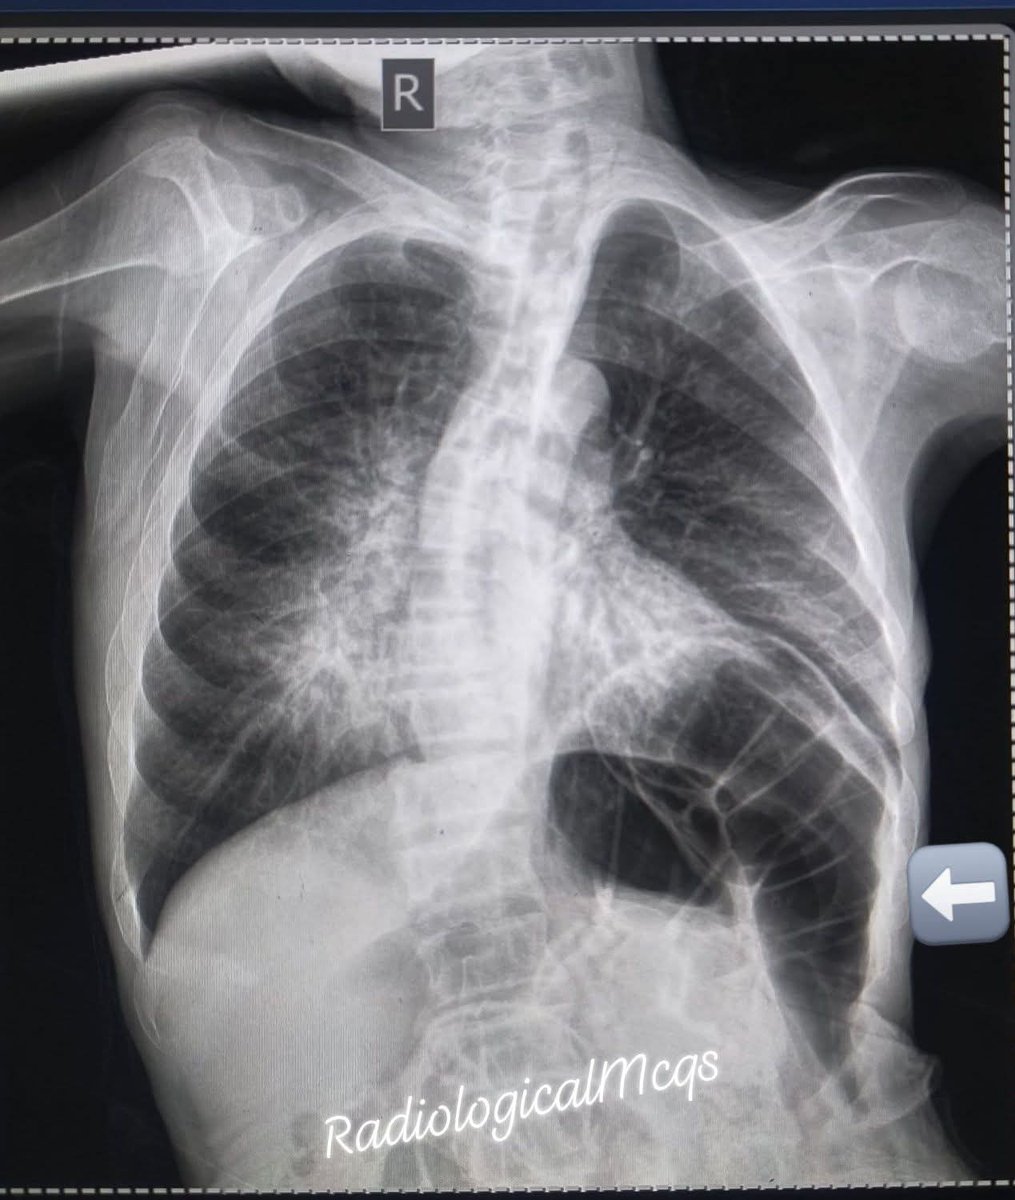

53 years old man Presented with chronic cough night sweats Associated with loss of weight.chest x ray was performed what are the findings and diagnosis? #radiographer #wellness #xray #health #diagnosis #radiology #pulmonology #respiratory @Dr_Chibuike_M @Dr_Shiv_kumar_

albertoortegana's tweet image. 53 years old man Presented with chronic cough night sweats Associated with loss of weight.chest x ray was performed what are the findings and diagnosis?

#radiographer #wellness #xray #health #diagnosis #radiology #pulmonology #respiratory